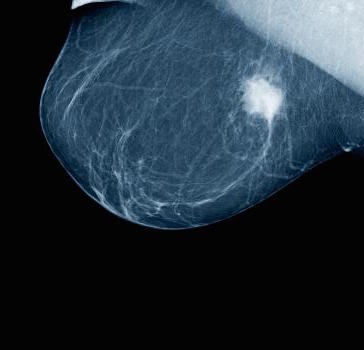

Then January the 3rd, the doctors visit. January 8th, the mammogram. I remember wanting to make a joke with a Facebook status about what a joyous experience mammograms are. Highly recommended. Not! But I didn’t. And then the next day, January 9th, I returned for the ultrasound and core biopsies.